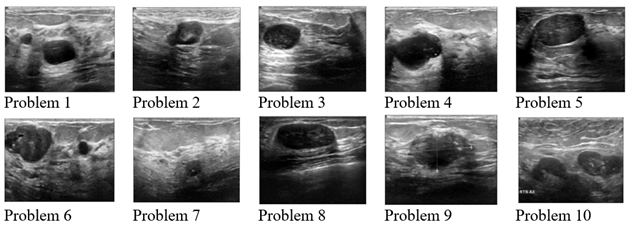

In Experiment 1, 10 original BUS images will be used as shown in Figure 1. The size of the original BUS images is 128 x 128.

All images in Figure 1 will be segmented by the existing model, CDSS,and the modified models:MCDSSG, MCDSSM, MCDSSW and MCDSSROF. For example, we illustrate two samples of segmentation results of Problem 1 and Problem 2 of Experiment 1 in Figure 2.

Figure 1. Test images in experiment 1.